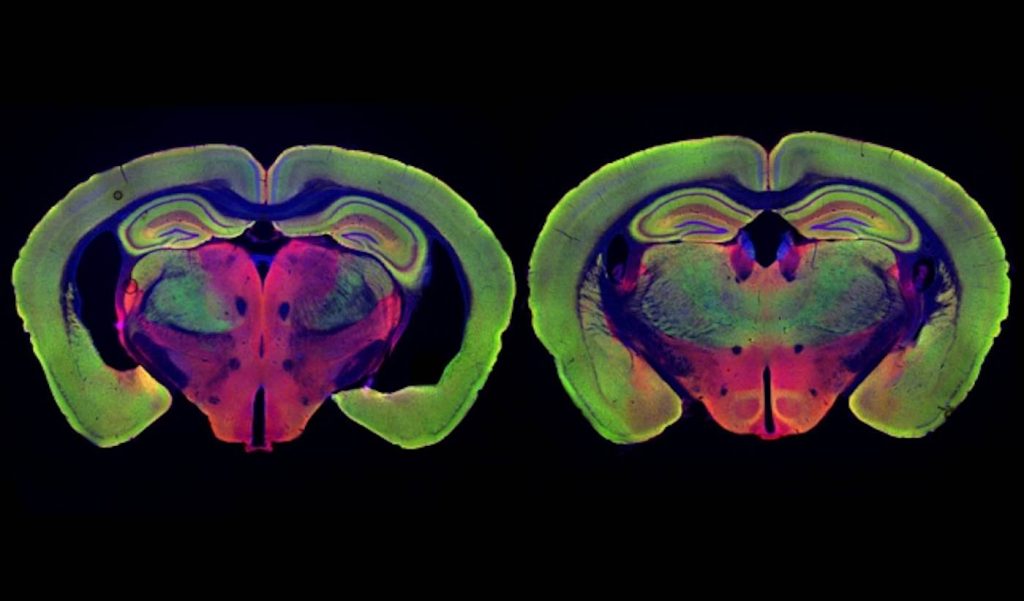

Photo by Chinnakkaruppan Adaikkan / MIT News

In their new study, the researchers wanted to delve deeper into how these beneficial effects arise. They focused on two different strains of mice that are genetically programmed to develop Alzheimer’s symptoms. One, known as Tau P301S, has a mutated version of the Tau protein, which forms neurofibrillary tangles like those seen in Alzheimer’s patients. The other, known as CK-p25, can be induced to produce a protein called p25, which causes severe neurodegeneration. Both of these models show much greater neuron loss than the model they used for the original light flickering study, Tsai says.

The researchers found that visual stimulation, given one hour a day for three to six weeks, had dramatic effects on neuron degeneration. They started the treatments shortly before degeneration would have been expected to begin, in both types of Alzheimer’s models. After three weeks of treatment, Tau P301S mice showed no neuronal degeneration, while the untreated Tau P301S mice had lost 15 to 20 percent of their neurons. Neurodegeneration was also prevented in the CK-p25 mice, which were treated for six weeks.